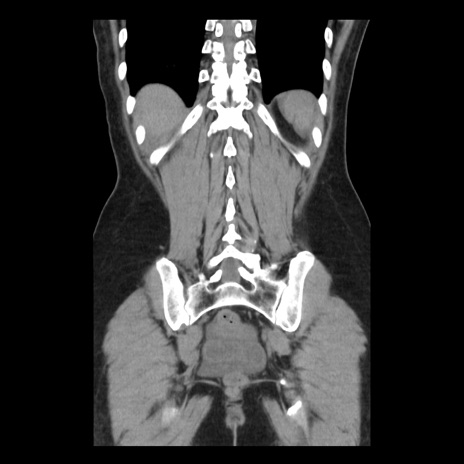

症例10(冠状断像)

【症例】 50歳代女性

【主訴】 腹痛

【現病歴】前日生レバーを食べた。今朝に排便あり。 昼前に突然発症の腹痛を生じ、当院救急外来を受診した。

【既往歴】 子宮筋腫にてで子宮全摘後

【身体所見】 意識清明、腹部:平坦、軟、下腹部やや左を中心に圧痛・反跳痛あり、筋性防御あり

【データ】WBC 7800、CRP 0.07